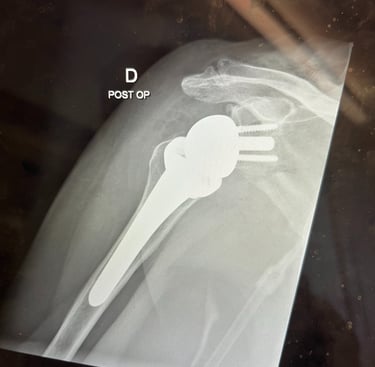

Spalla

Mi occupo del trattamento delle principali patologie della spalla, con particolare esperienza nella protesica di spalla (anatomica e inversa). Tratto inoltre instabilità di spalla, lesioni della cuffia dei rotatori e traumatologia della spalla, con l’obiettivo di ripristinare la funzione articolare e ridurre il dolore attraverso tecniche chirurgiche moderne e personalizzate.